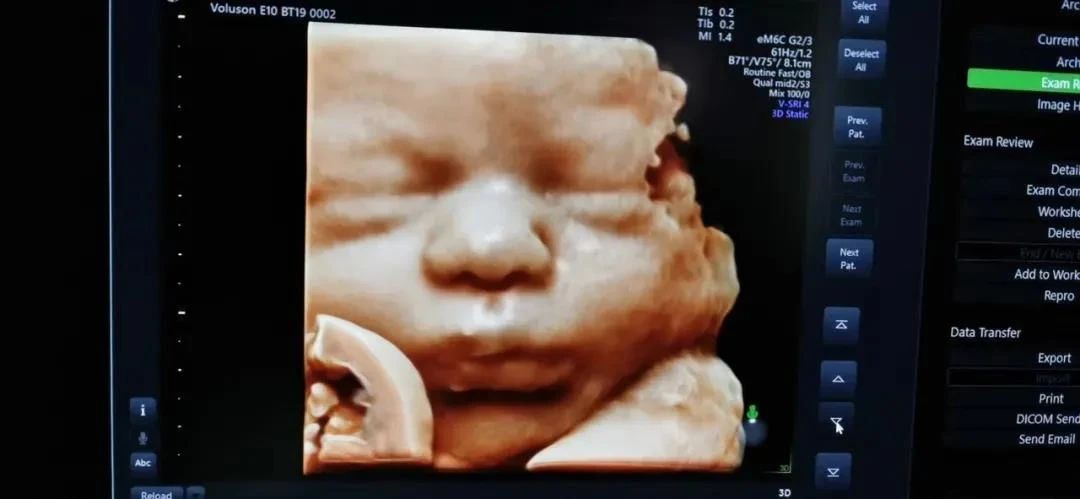

其次,安琪兒使用的彩超設備是GE-E10,也是成都更早擁有GE-E10的醫療機構,胎兒排畸檢查更強大,獨立成像更清晰。孕媽媽還可以通過四維彩超獲得寶寶人生第一張照片哦!

就診時,準爸爸也可以和準媽媽一同進入B超室,一起通過屏幕,看看寶寶的小手小腳,和寶寶say一聲hi,說不定寶寶還會回應一個俏皮的“鬼臉”哦~